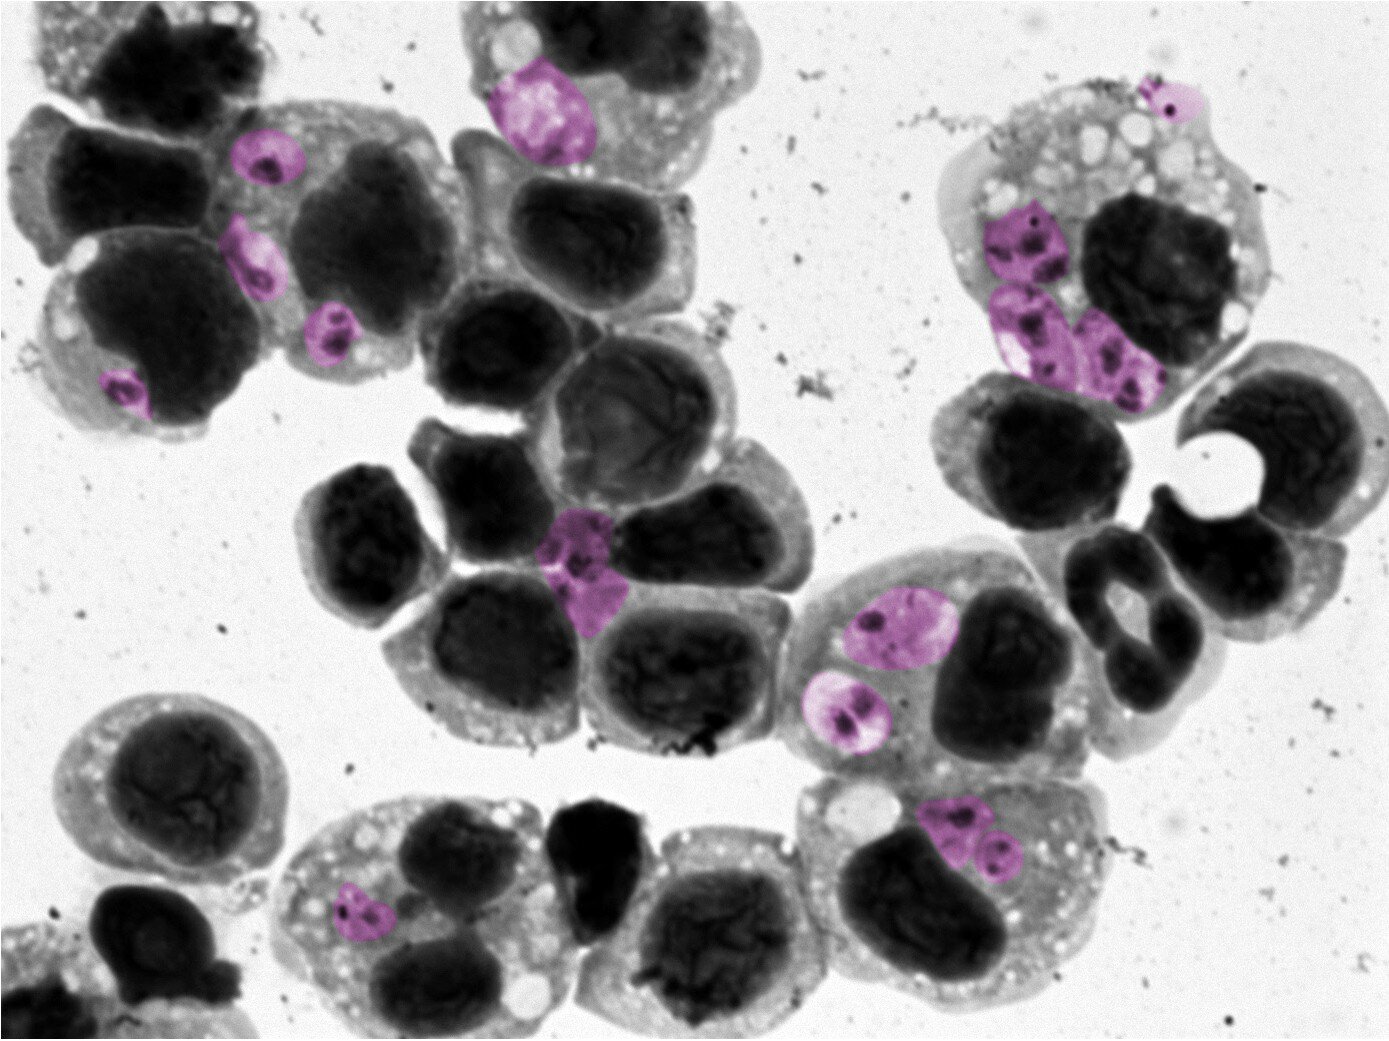

Près d’un million de personnes dans le monde sont en proie à chaque année par la leishmaniose cutanée, une infection cutanée dévastatrice causée par le parasite de Leishmania. Affectant principalement les populations vulnérables dans les régions tropicales et subtropicales comme l’Afrique du Nord et l’Amérique du Sud, cette maladie prospère dans les zones marquées par la malnutrition, les logements médiocres et le déplacement de la population. Sans traité, cela peut entraîner des cicatrices à vie, un handicap débilitant et une stigmatisation sociale profonde. Malgré son impact mondial, il n’y a pas de vaccin – et les traitements existants sont inefficaces, toxiques et difficiles à administrer.

L’équipe a constaté que les patients qui n’avaient pas répondu à l’antimoniate de méglumine ont montré un schéma distinctif dans leur système immunitaire, un état inflammatoire soutenu appelé réponse d’interféron de type I. Cette réponse est généralement une partie cruciale du système de réponse précoce du corps contre les virus, aidant les cellules à détecter un pathogène et à recruter des ressources pour lutter contre elle.

« Cette réponse élevée d’interféron de type I a été observée à travers plusieurs types de cellules immunitaires innées que nous avons analysées dans des échantillons de sang des patients.